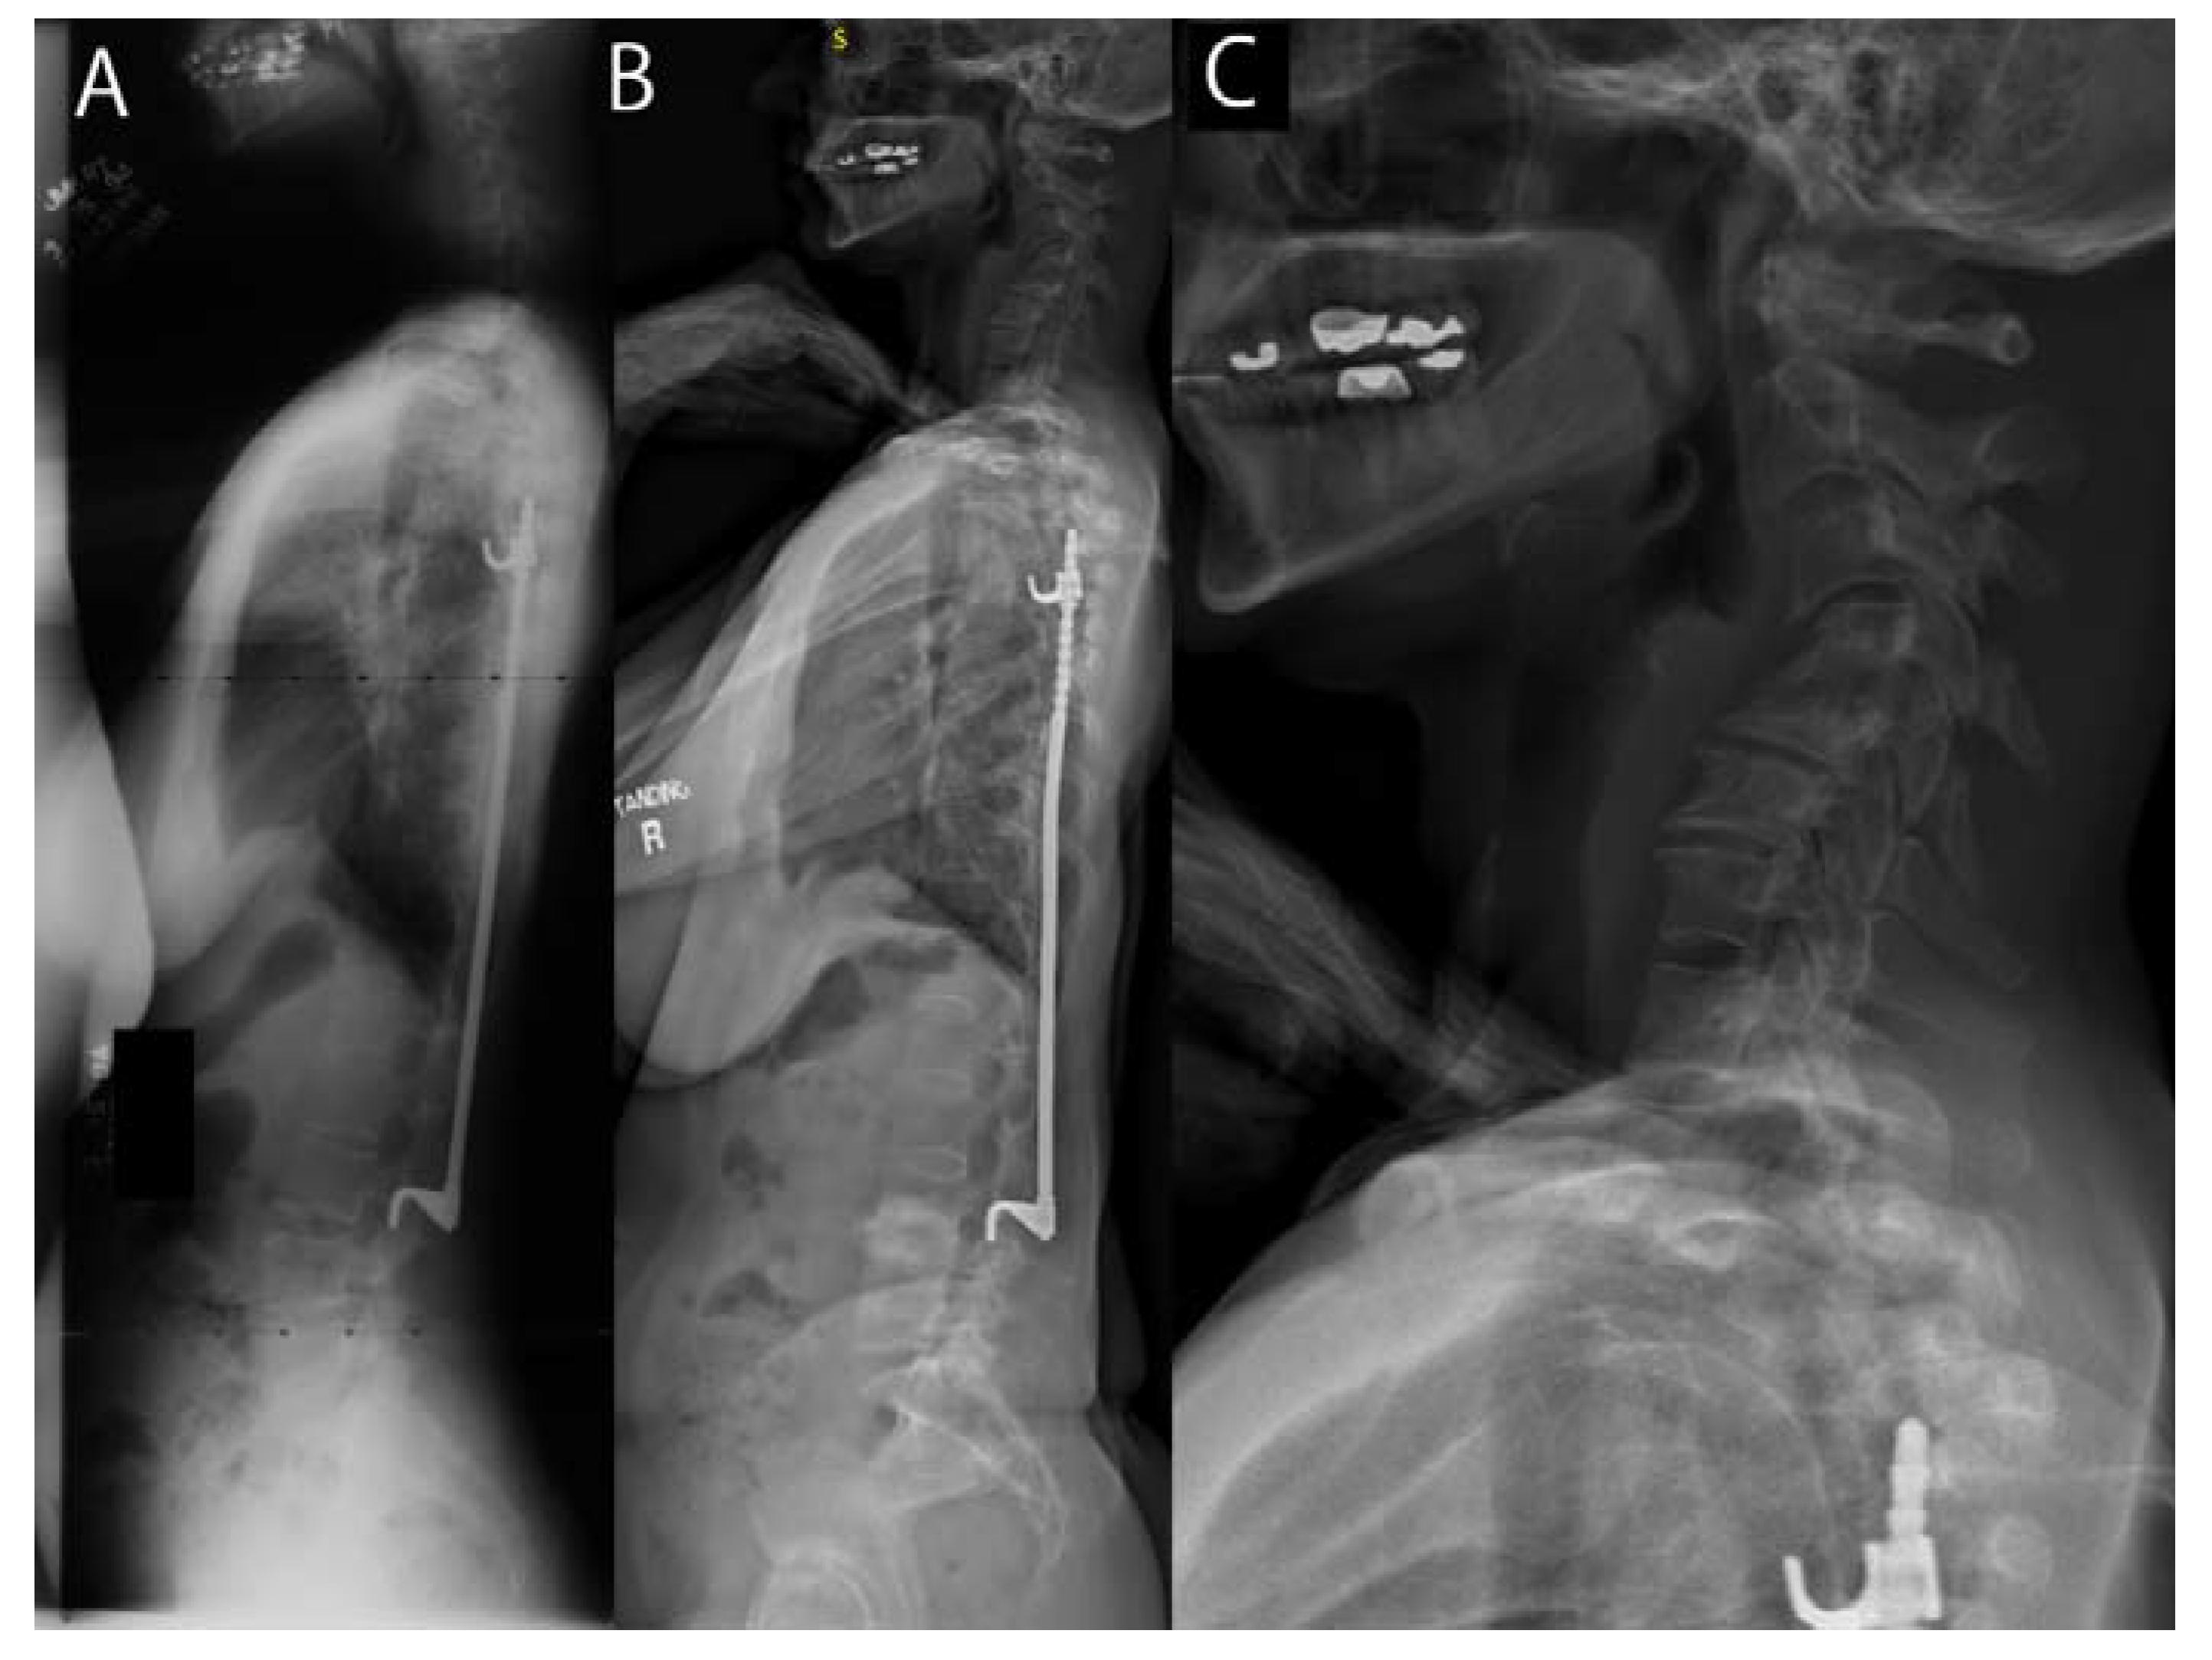

From www.mdpi.com

JCM Free FullText At Mean 30Year FollowUp, Cervical Spine Cervical Arthritis At 30    neck arthritis, also called cervical spondylosis, is a common condition that occurs when the cartilage and bones in the neck gradually wear down over time, leading to joint inflammation, pain,. The discs may naturally dry out and shrink over time, which can lead to bone spurs and other osteoarthritis signs and symptoms. Symptoms include neck pain, stiffness, headache, arm. Cervical Arthritis At 30.

From www.semanticscholar.org

Figure 1 from Rheumatoid arthritis of the cervical spineclinical Cervical Arthritis At 30    webmd provides information on cervical osteoarthritis, also known as cervical spondylosis, including causes, symptoms, and treatments.   neck arthritis, also called cervical spondylosis, is a common condition that occurs when the cartilage and bones in the neck gradually wear down over time, leading to joint inflammation, pain,. Symptoms include neck pain, stiffness, headache, arm or leg weakness, and referred. Cervical Arthritis At 30.